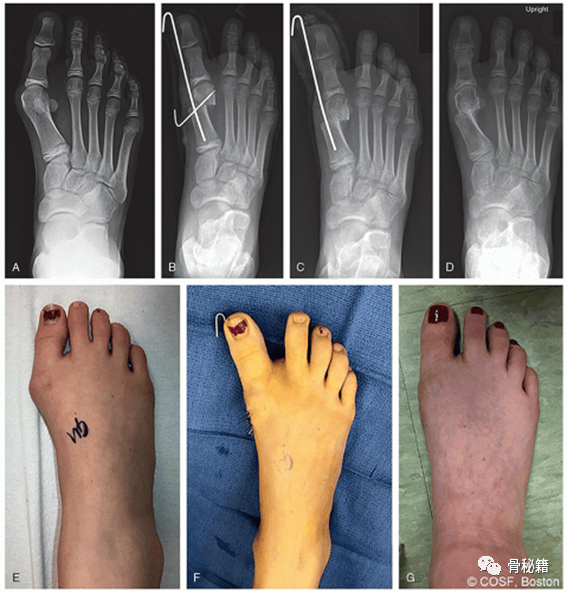

一名女孩,右侧拇外翻疼痛。

A,术前站立前后位 (AP) 射线照片。

B,即刻术后 X 光片。C,斜线移除后 4 周的术后 X 光片。

D,术后 4 个月的 X 光片,截骨愈合,矫正良好。

EG,同只足术前、术中和术后 4 个月的临床照片。